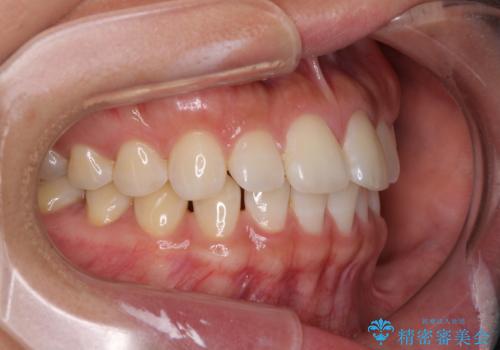

【モニター】前歯のすきっ歯をインビザラインで改善

- 上顎前歯の隙間と口元の突出感を気にして来院された患者様です。

高校生の時に行った矯正治療の後戻りであり、歯列不正は軽度であったので、インビザラインにて治療を行うこととしました。